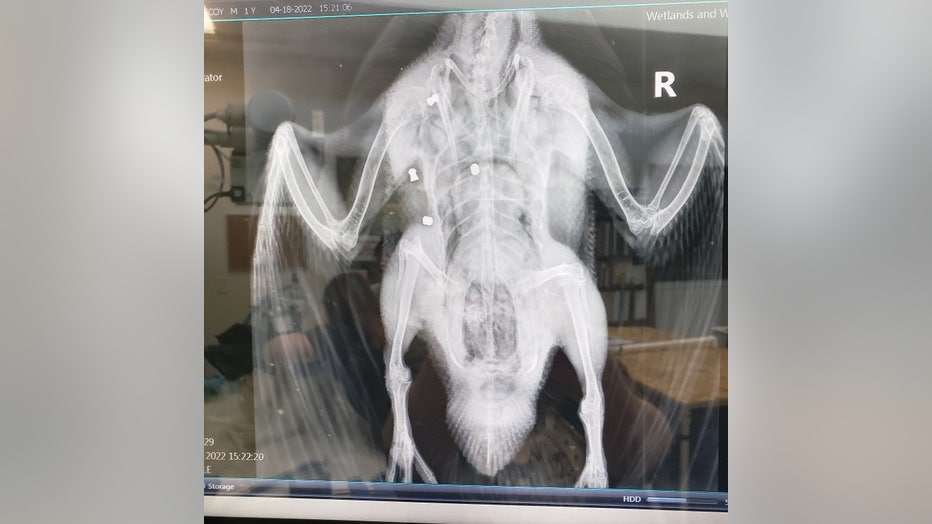

The x-ray of Grace the Muscovy duck, shot and killed at TeWinkle Park in Costa Mesa.

The wildlife center says it's assisting the Costa Mesa Police Department by x-raying and removing the bullets from the killed ducks.